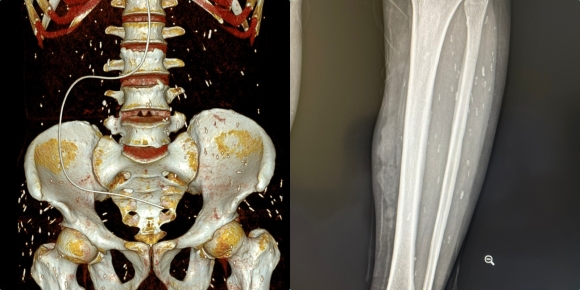

Kết quả chụp CT-Scanner ổ bụng cho thấy hình ảnh giãn đài bể thận niệu quản phải do sỏi niệu quản 1/3 giữa, sỏi thận hai bên, sỏi túi mật, thoát vị bẹn phải. Đặc biệt hơn, các bác sĩ còn phát hiện ấu trùng sán rải rác khắp cơ thể, đường kính 3-5mm.

Hình ảnh sán ký sinh khắp cơ thể bệnh nhân (Ảnh: BVCC).